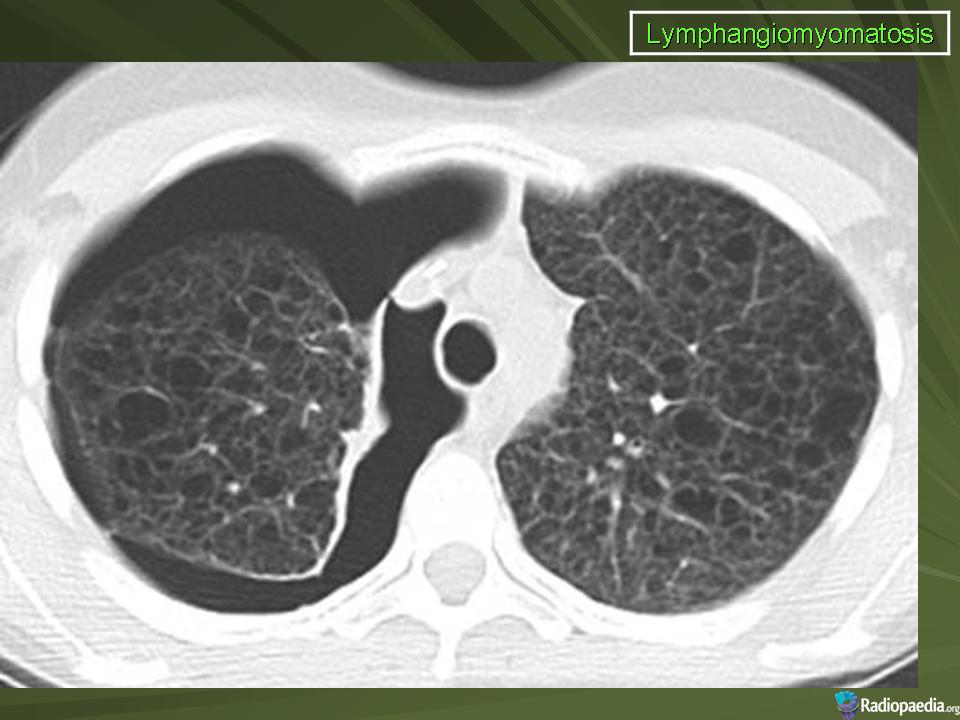

лимфангиолейомиоматоз

Типичный пример патологии при которой основным патерном являются кисты - :

Лимфангиомиоматоз.

Из архива AFIP. Лимфангиолейомиоматоз.

Лимфангиолейомиоматоз.